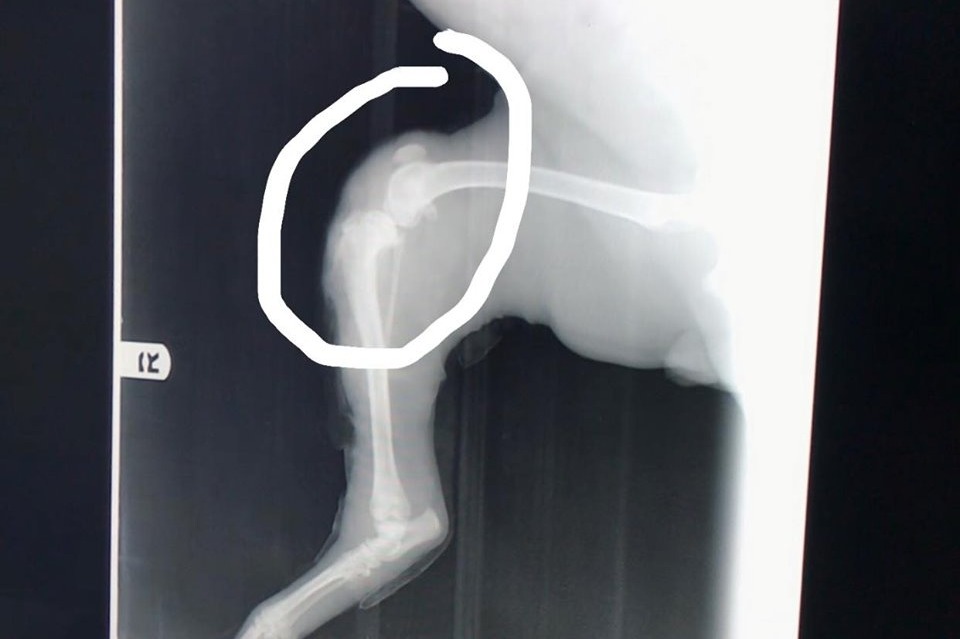

The dog was hit by a car and sustained some serious injuries to her legs. The young lady’s name is Sarai. She named the dog Merida. Sarai took Merida to the vet in San Felipe, but after they told her that they will have to amputate both Merida’s legs, she drove all the way to Mexicali to see another vet. The vet in Mexicali said that Merida will need three surgeries, and they are certain they can save her legs.